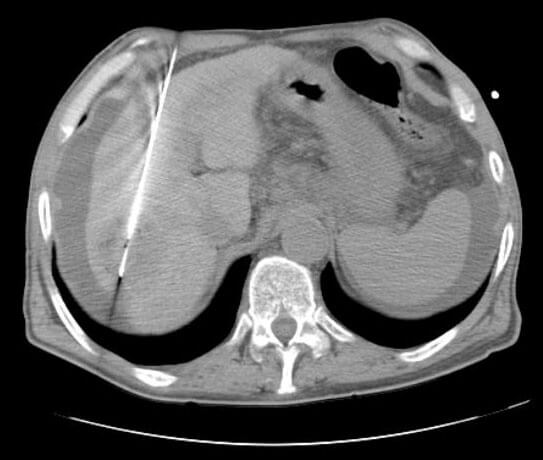

Ablation

Ablation is a treatment for primary and metastatic cancer involving the liver, lung, kidney, or bone. Ablation is a procedure performed by IR that involves placement of a needle-like probe into the tumor using CT or ultrasound for guidance. Once the probe is in place, the tumor is exposed to extremes of temperature; microwave and radiofrequency ablation expose the tumor to very high temperatures and cryoablation exposes the tumor to very low temperatures.